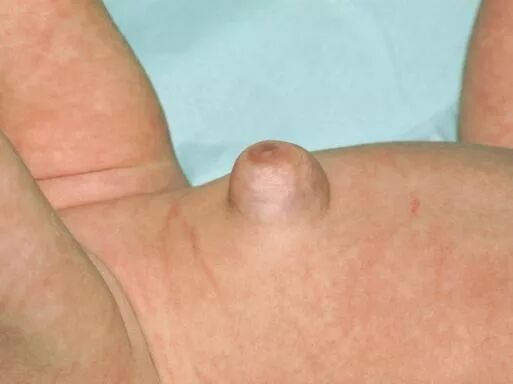

脐疝

当娃还小的时候,脱落后脐部瘢痕是一先天性薄弱口,且两侧腹直肌前后鞘在脐部未合拢;随着婴儿的成熟, 这个开薄弱口本应随着腹部肌肉的合并而关闭。但有些小宝宝的肌肉合并的不及时或比较松懈,就给了腹腔内容物(尤其是肠子)顶出的机会。

女宝宝得脐疝得可能性会比男宝宝大一些。

大部分的宝宝会在2~3岁以内自行愈合,有的会延长至5岁。平时家长注意观察就好。但也有疝囊直径大于3cm的,建议手术治疗。